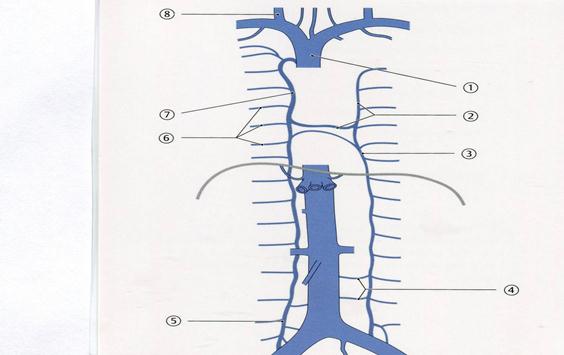

+А.Балтыр

43. Төменде көрсетілген суреттегі белгіленген №7венаны атаңыз.

С. Жоғарғы қуыс

+Е. Сыңар